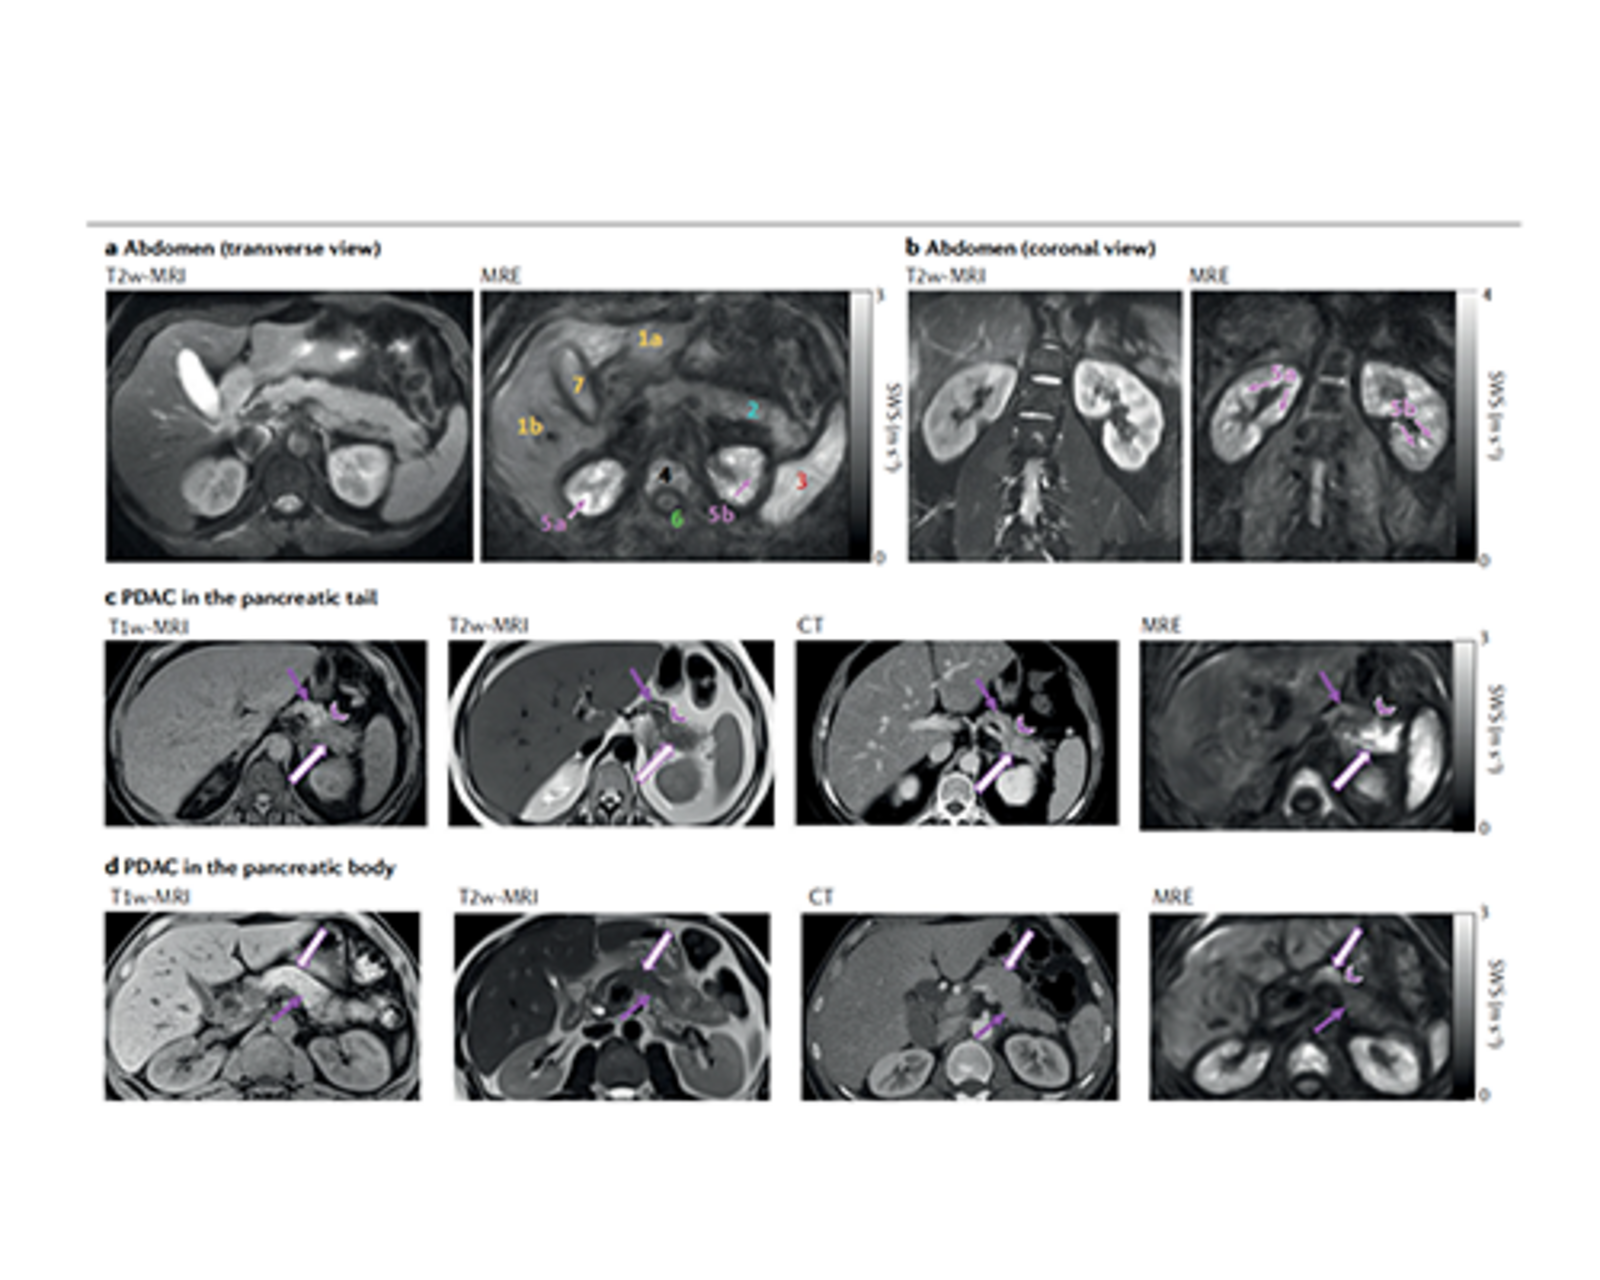

Mapping of shear wave speed as surrogate of stiffness in abdominal organs based on tomoelastography compared with conventional imaging such as T2-weighted magnetic resonance imaging (MRI) and T1-weighted MRI and computed tomography.

https://doi.org/10.1038/s42254-022-00543-2. Copyright: Ingolf Sack

Investigation of Brain’s Structure-Function Relationship in Glioma Patients using MRE

Brain | Sensing – Vibrations The effects of brain tumors on brain function are difficult to predict due to the complexity of individual brain networks and the brain's potential for functional reorganization. Invasive and noninvasive brain imaging techniques can help to better understand the effects of brain tumors on brain networks and improve treatment efficacy and levels of control.